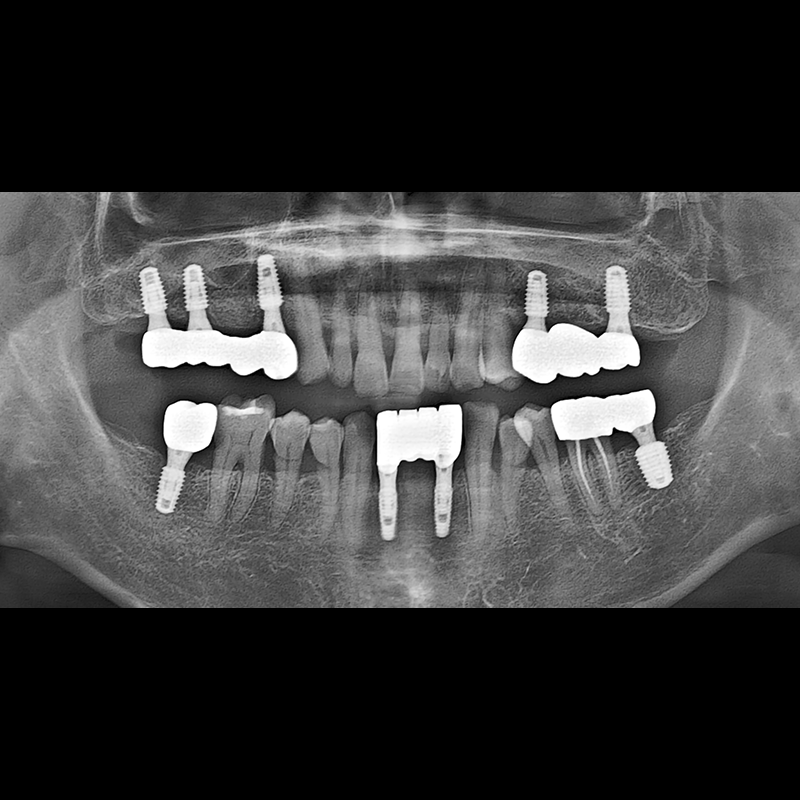

BEFORE AFTER

种植牙前后的照片 2025.05.30

在缺失的牙齿部分和难以挽救的牙齿位置植入了种植牙。